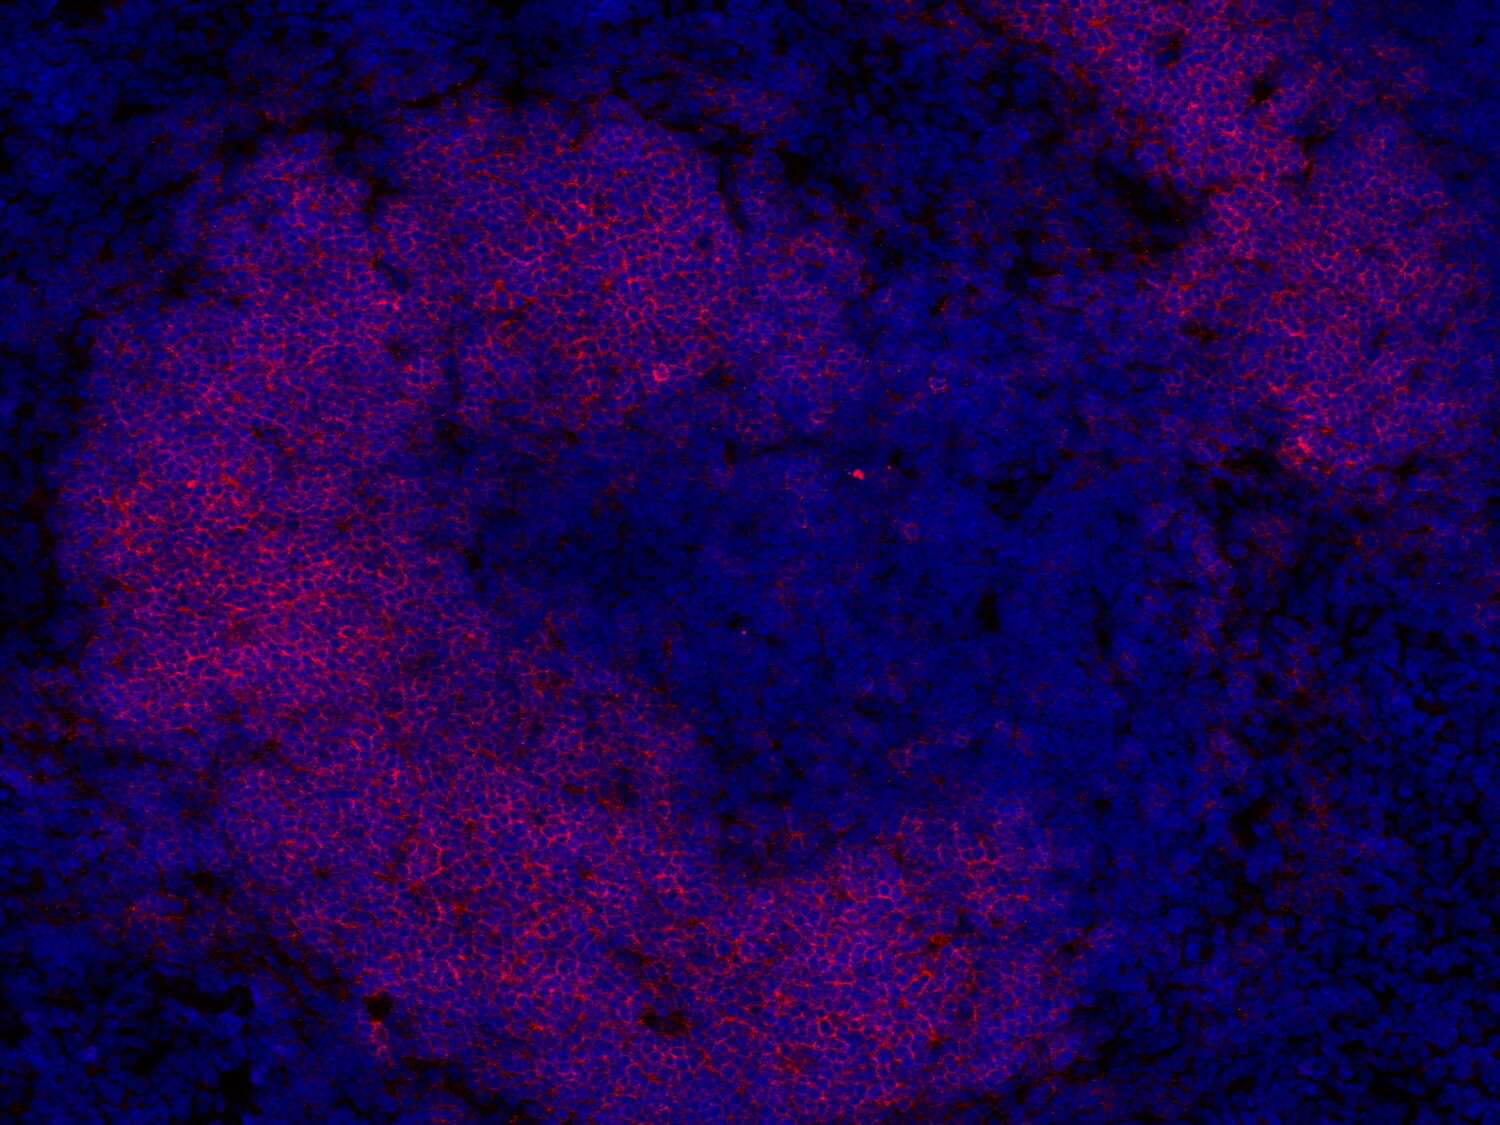

Fluorescent double staining for CD19 (red) and CD3e (green) visualizes B-cell and T-cell populations in the mouse spleen